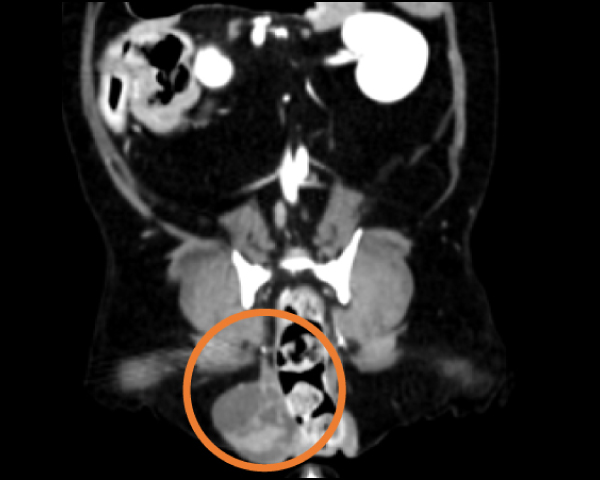

造影CT検査にて腫瘤の浸潤を評価

腹腔鏡を用いた副腎腫瘍摘出術